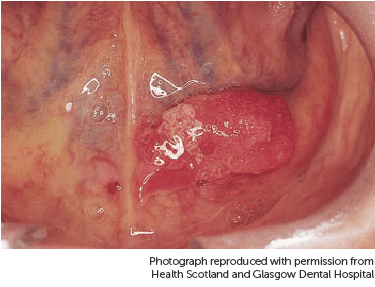

The picture below shows a speckled ulcer on the inside of the cheek.